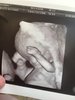

U nas wieści super. Wszystko rozwija się idealnie. Wyniki prenatalnych tez wszystkie piękne. Bardzo niskie wskaźniki chorób. Cała anatomia idealna. Jedyne co to przez ta moja żółta wydzielinę dostałam skierowanie na badanie do onkologa zeby obejrzał szyjkę pod mikroskopem zeby na 100% upewnić się ze wszystko jest w porządku bo posiewy wyszły dobrze. Załączam fotki w 3D

.

Następna wizyta za 3 tygodnie i wtedy podobno już na 100% płeć mi powie![]()